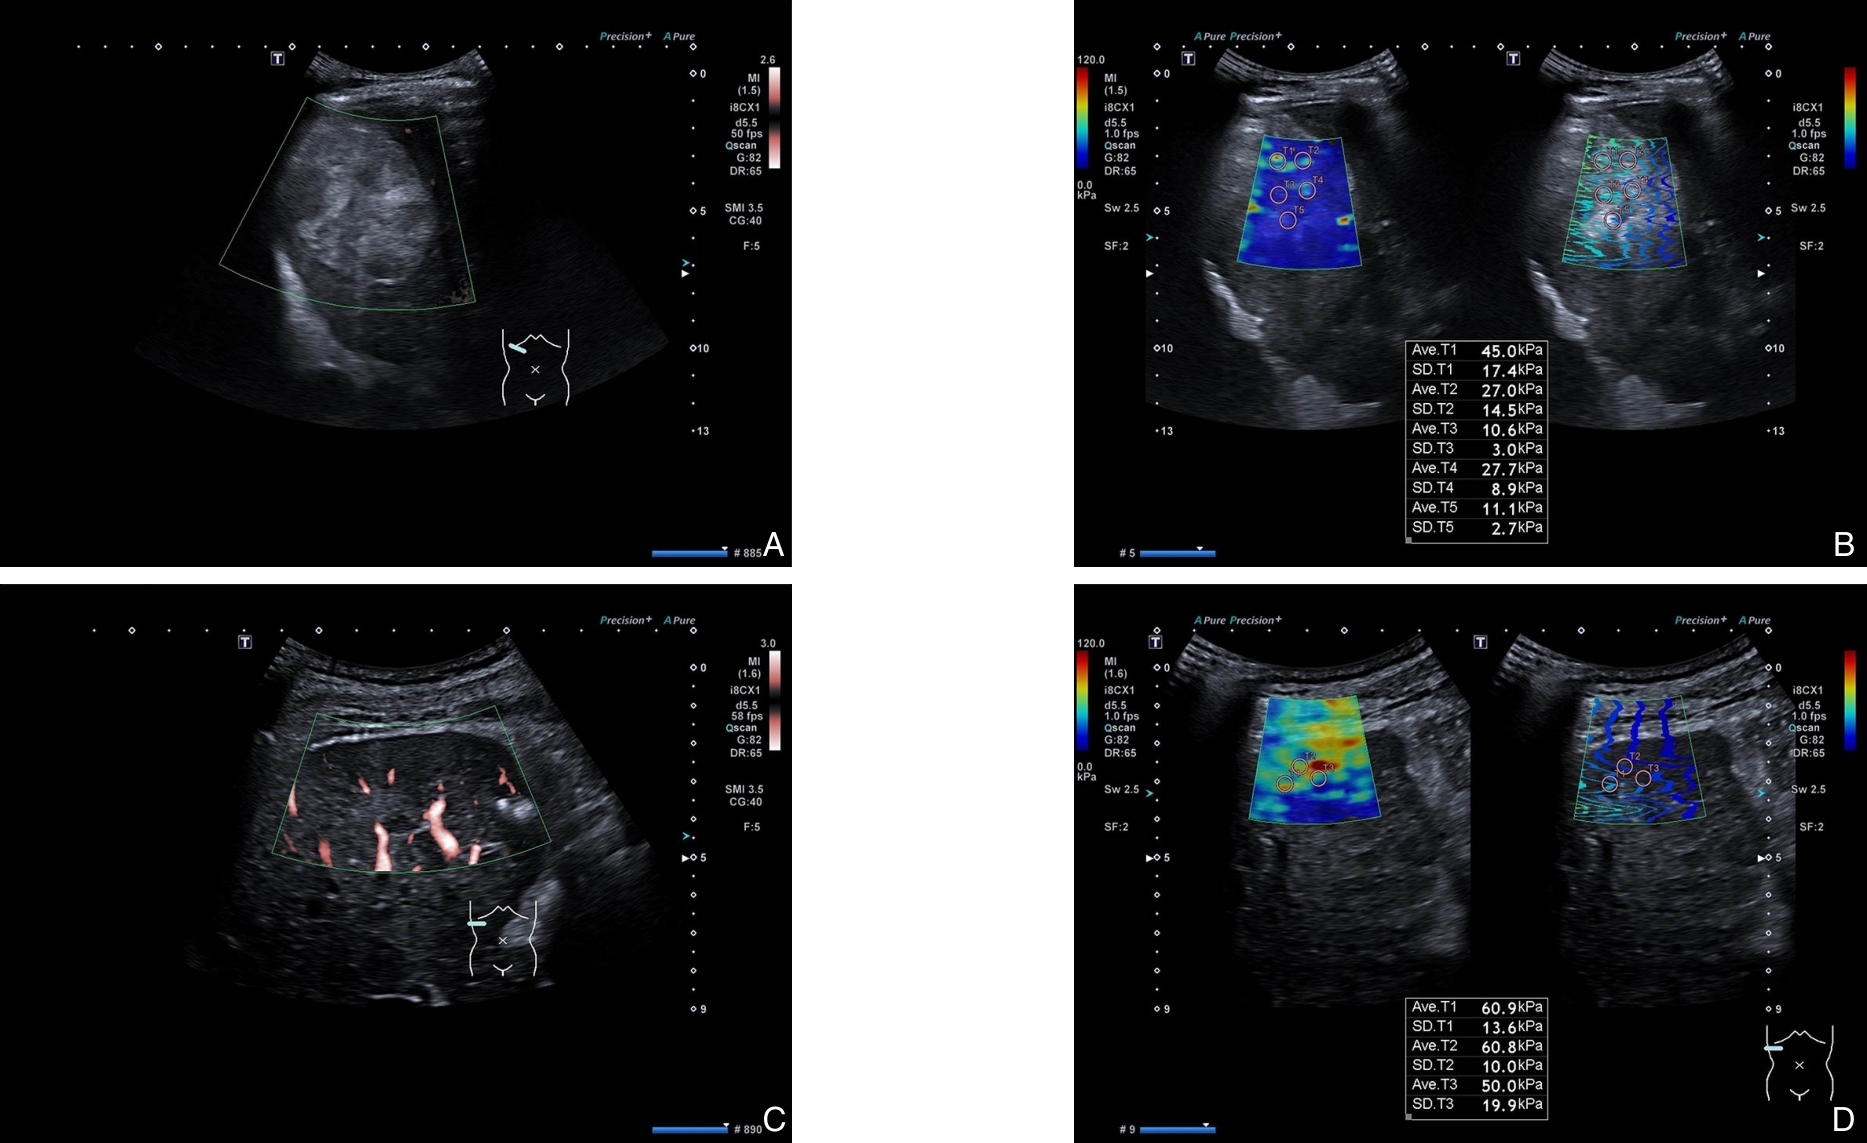

摘要:背景与目的 中晚期肝癌患者接受经导管动脉化疗栓塞(TACE)联合射频消融(RFA)序贯治疗后复发率仍较高,术前缺乏可靠的风险分层工具。本研究基于超微血管成像(SMI)与剪切波弹性成像(SWE)构建多模态超声联合机器学习模型,并结合SHAP算法进行可解释性分析,旨在预测中晚期肝癌患者TACE-RFA序贯治疗后的复发风险。方法 回顾性纳入2022年6月—2024年6月215例BCLC B/C期肝癌患者,按7∶3比例分为训练集(n=150)与测试集(n=65)。收集临床资料、生化指标及SMI、SWE超声特征。采用随机森林、支持向量机及极限梯度提升(XGB)进行变量重要性排序,结合交集筛选及双向逐步Logistic回归确定独立预测因子。构建7种机器学习模型,通过10折交叉验证优化参数。以曲线下面积(AUC)、敏感度、特异度、Brier评分及决策曲线分析(DCA)评价模型性能,并利用Tree SHAP解释模型输出。结果 术前肿瘤最大径、甲胎蛋白(AFP)、最大弹性模量(Emax)、弹性比值(Eratio)及血管形态为独立预测因子。XGB模型在训练集与测试集中的AUC分别为0.989和0.959,Brier评分分别为0.034和0.056,DCA显示其在较宽阈值范围内具有最佳净收益。SHAP分析表明,高Eratio、高AFP、血管形态不规则及肿瘤最大径较大显著增加复发风险,而较低Emax与复发风险降低相关。结论 基于SMI-SWE多模态超声构建的XGB模型可较准确预测中晚期肝癌患者TACE-RFA序贯治疗后的复发风险,具有良好的临床应用潜力。SHAP分析增强了模型的可解释性,为术前个体化风险评估和治疗决策提供了量化依据。